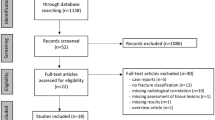

The exclusion criteria were as follows: (1) open tibial diaphyseal fracture; (2) fasciotomy due to a diagnosis of acute compartment syndrome (ACS); (3) open reduction during surgery; (4) MR imaging contraindications (e.g., pacemaker); and (5) vascular and nerve damage to the affected limb. Finally, a total of 51 patients were recruited into the study cohort (Fig. 1).